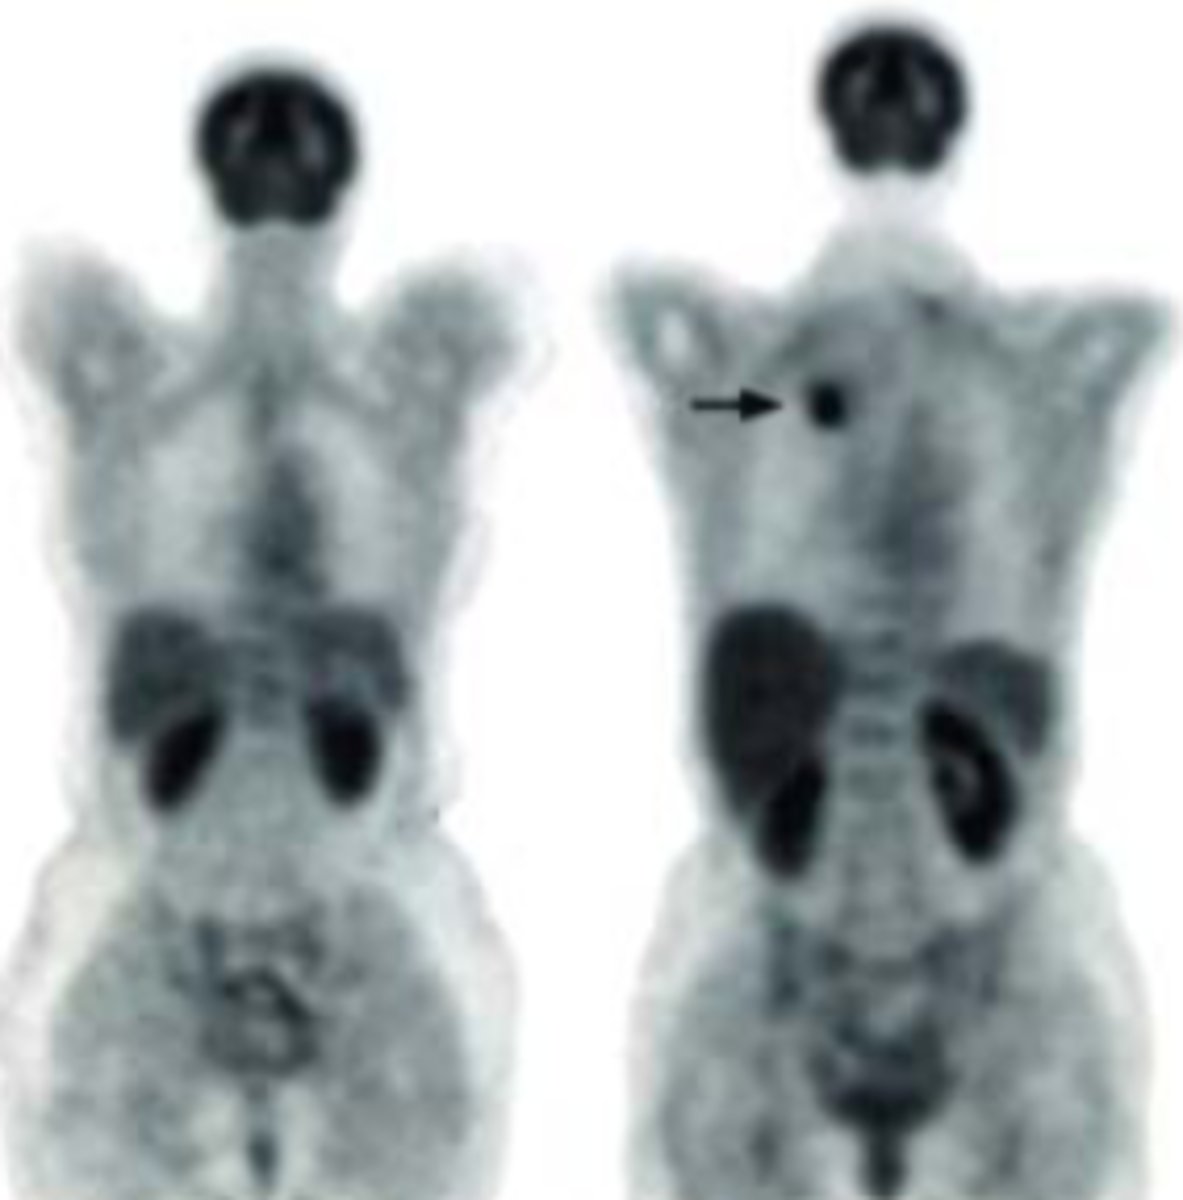

Single Photon Emission Computed Tomography.

How does SPECT imaging differ from planar imaging?

SPECT creates 3D images by using a single photon that is absorbed by a rotating single head or 2/3 head gamma camera to collect data from multiple angles, producing a series of anatomical slices.

What is a common application of SPECT imaging?

Brain scan.